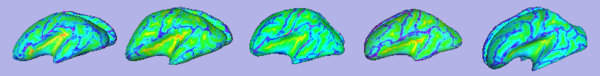

- 1.9. Sulcal depth computation

- Sulcal depth computation using genus-zero surface and inflated one

- Tool: MeshMath (UNC Slicer3 external module)

- 2. Particle-based shape correspondence

- Correspondence on inflated surfaces using particle system

- 2.2. Correspondence optimization

- Particle-based shape correspondence optimization (using sulcal depth) with Procrustes alignement

- Tool: ShapeWorksRun (Utah Slicer3 external module)